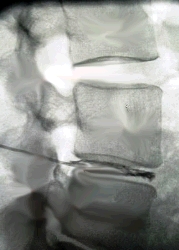

DISKOGRAPHIE |

| Die Darstellung der Bandscheibe mittels Einspritzung eines Kontrastmittels direkt in den Bandscheibenraum. Das Kontrastmittel breitet sich durch die Punktion aus und zeigt im Röntgenbild die Bandscheibe und ev. pathologische Veränderungen wie z.B. einen Bandscheibenvorfall. |